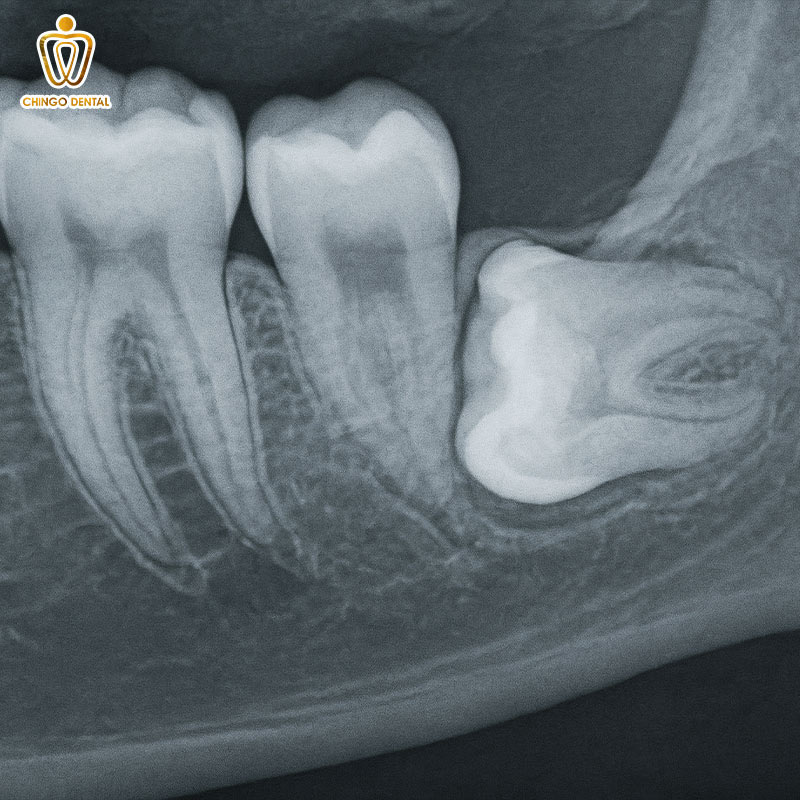

Răng số 8 mọc ngầm: “Bom nổ chậm” dưới nướu

Đây là tình trạng răng hoàn toàn bị bao phủ bởi xương hàm hoặc mô nướu. Không thể nhìn thấy bằng mắt thường. Khách hàng chỉ phát hiện ra khi đi chụp X-quang hoặc khi đã xảy ra biến chứng nặng.

Răng mọc ngầm trong xương: Chiếc răng nằm hoàn toàn trong xương hàm. Nếu không can thiệp, nó có thể hình thành nang thân răng, làm hỏng xương hàm xung quanh.

Răng mọc ngầm trong lợi: Răng đã thoát khỏi xương nhưng bị mô lợi dày che phủ. Đây là “ổ” chứa vi khuẩn gây nhiễm trùng tái đi tái lại.

Dấu hiệu nhận biết: Cảm giác đau âm ỉ vùng góc hàm nhưng không thấy răng nhú lên. Đôi khi gây đau lên thái dương hoặc ê buốt các răng phía trước mà không rõ nguyên nhân.

- Thăm khám và chụp X-quang: Xác định chính xác vị trí và hướng mọc lệch của răng.